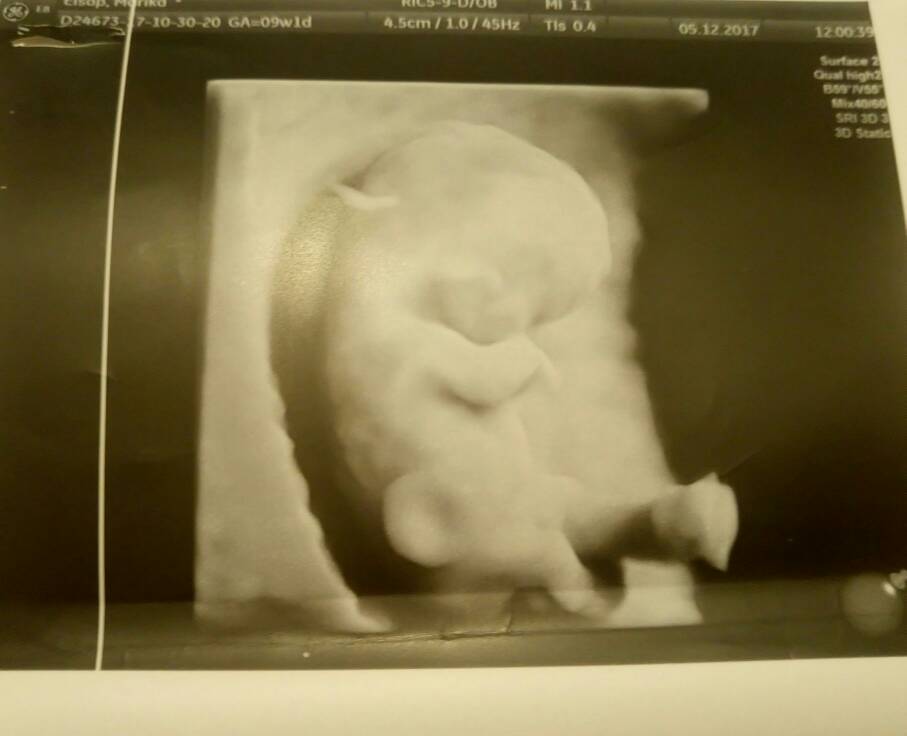

Dzidziuś ma się świetnie

27.06.17 Anastazja [*]

@Marika92 śliczna dzidzia

super że jest wszystko dobrze trzymam kciuki i głęboko wierzę że tak już zostanie